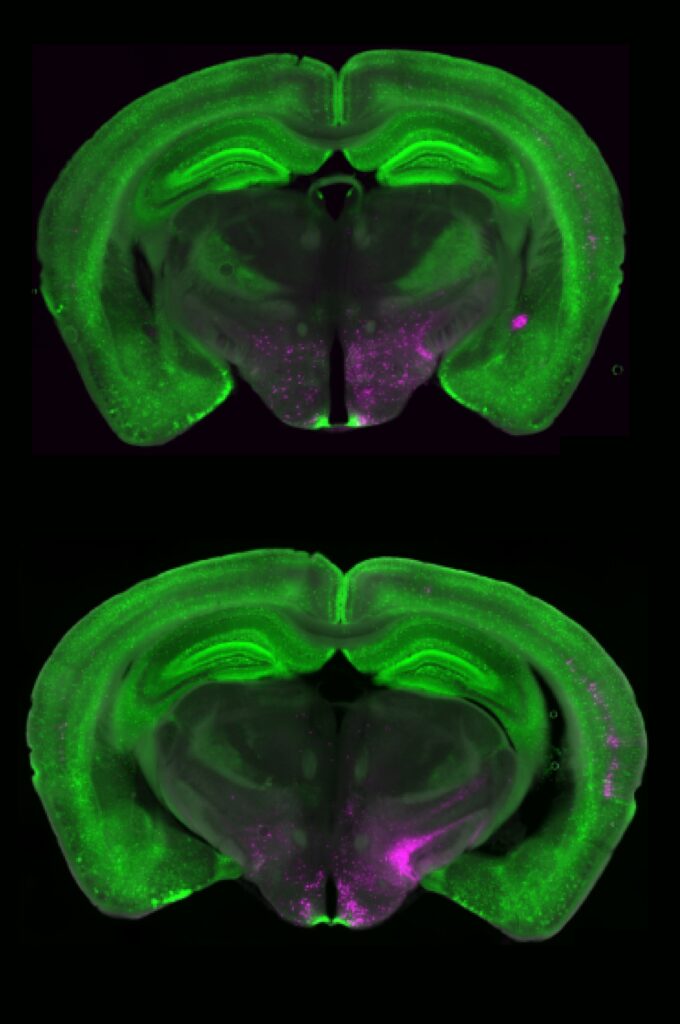

To track these elusive neurons, the researchers used calcium imaging, a powerful technique that allows them to watch neurons fire in real time in animal models. The patterns were astonishing.

In response to acute pain, the Y1R neurons lit up briefly — like a spark. But during chronic pain, they stayed active, continuously firing in what neuroscientists call a “tonic” state. This steady hum of neural activity was like an idling engine — the pain persisted even when the external source of injury was gone.

When the researchers examined the structure of the Y1R neurons more closely, they found something unexpected — these neurons weren’t neatly clustered together. Instead, they were scattered across many different cell types, forming a mosaic pattern throughout the brainstem.

“It’s like looking at cars in a parking lot,” Betley explains. “We expected all the Y1R neurons to be a cluster of yellow cars parked together, but they were like yellow paint splattered across red, blue, and green cars.”

This scattered organization may give the brain remarkable flexibility. It means that pain can be modulated across multiple circuits simultaneously, depending on context — whether the pain is physical, emotional, or environmental.